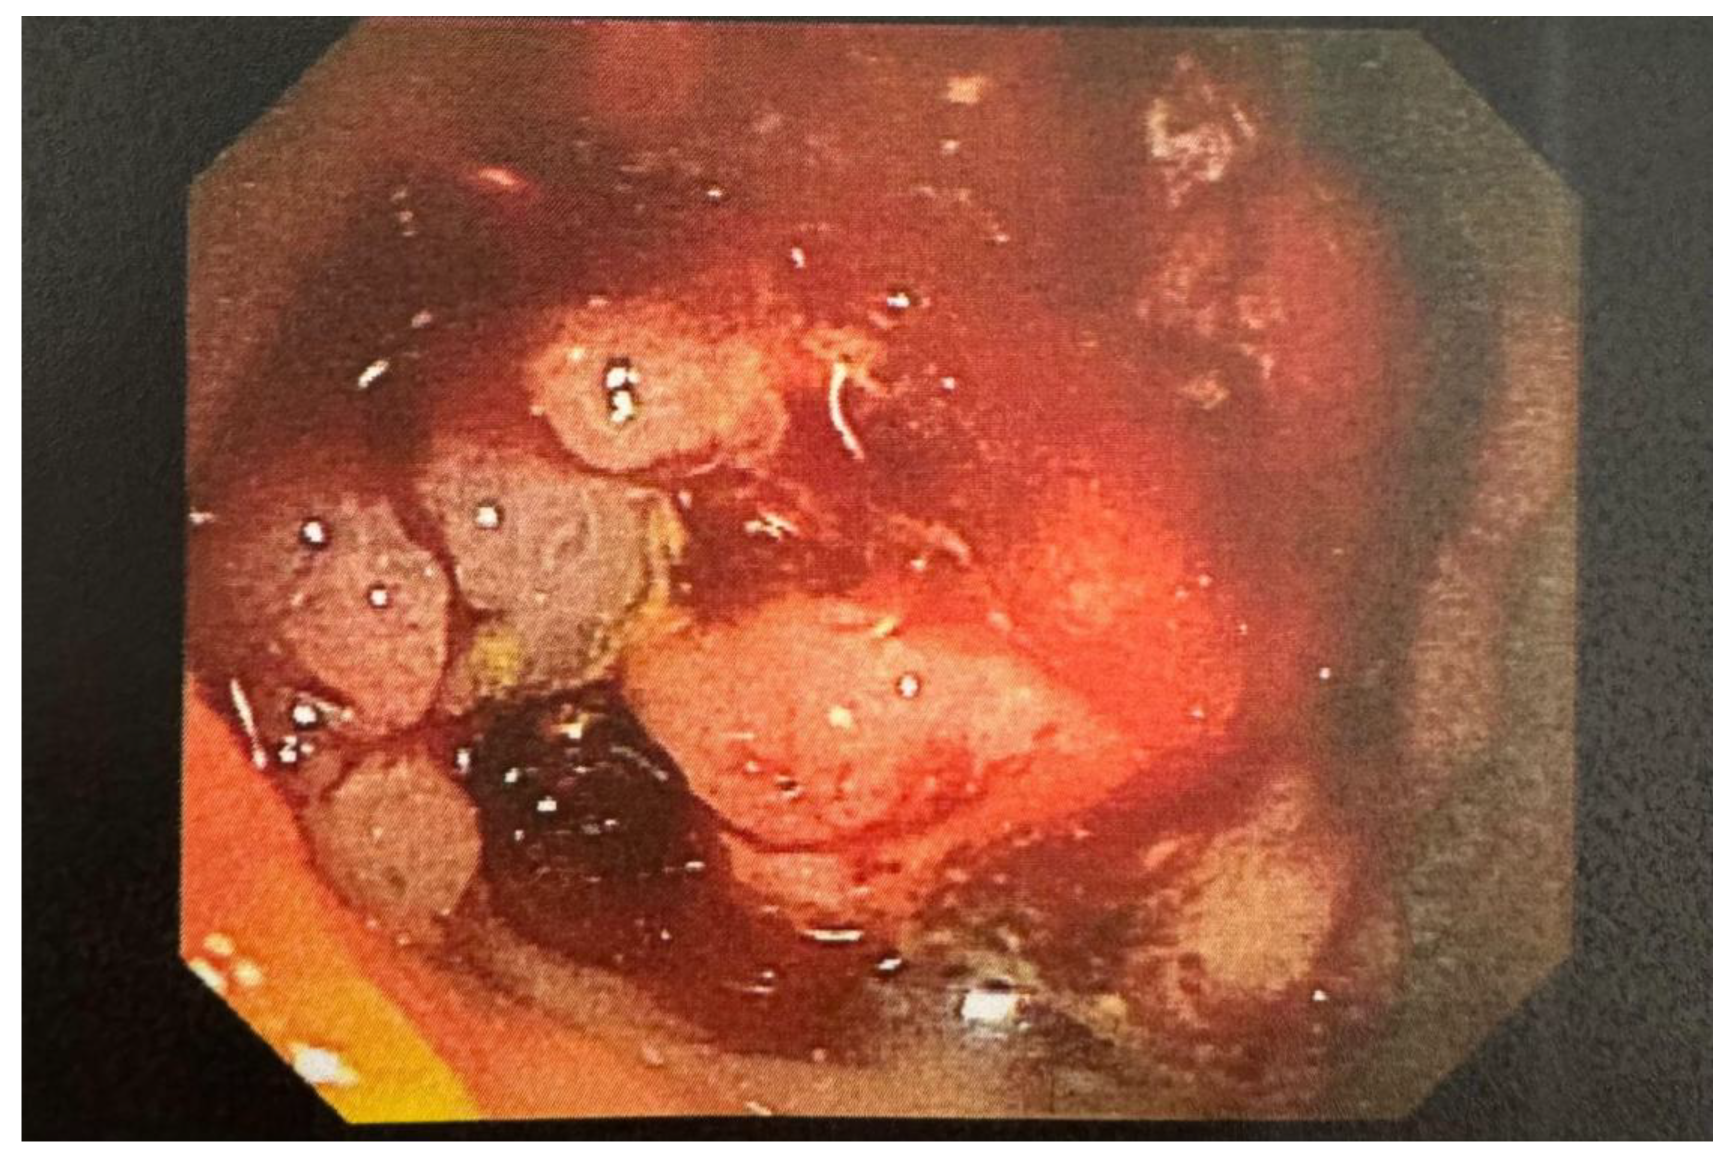

Case Presentation: